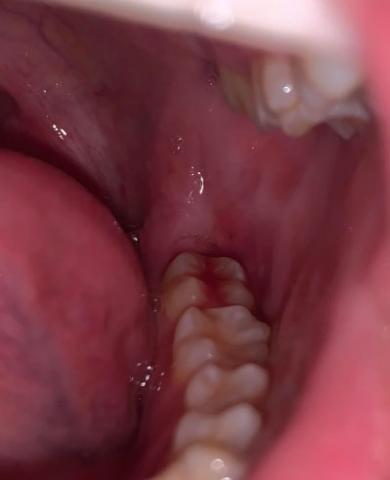

Bleeding Gums Near Molars - Zoomed Dental Case and Scaling Analysis

Focused Area: Posterior teeth (molar region) and surrounding gingival tissue

Localized gum redness and bleeding near the molar gum margin

Soft tissue appears inflamed and irritated

Area is difficult to clean, making it prone to plaque retention

No obvious fracture or large cavity visible at this zoom level

Possible early pocket formation cannot be ruled out without probing

Plaque-induced gingivitis in the molar region

Localized gingival trauma or inflammation

Early risk of posterior periodontal disease if untreated